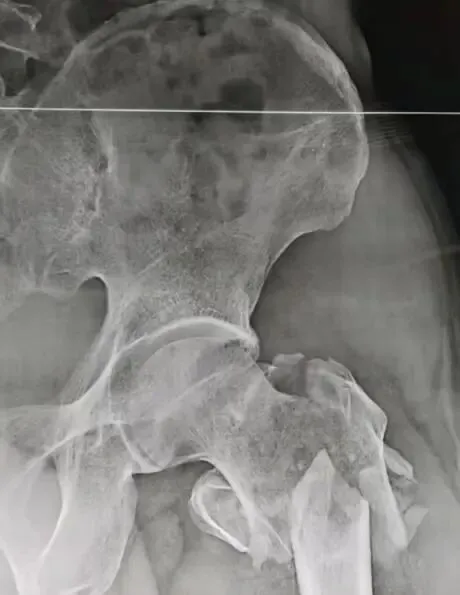

尿路结石是泌尿外科最常见的疾病,调查发现,每20个人中就有1个人可能患有该病,但是很多人平常不够重视,都等到“痛不欲生”被送入急诊,才会意识到及时治疗的重要性。